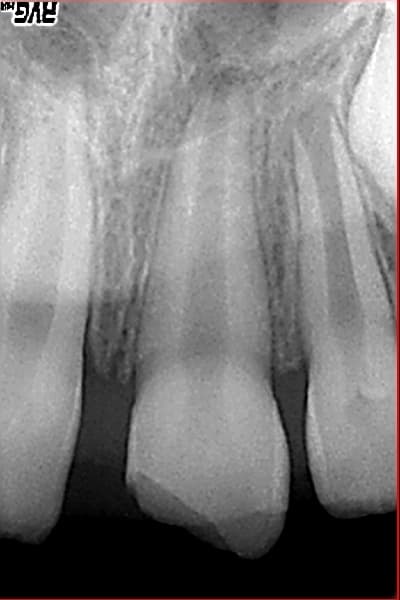

Jeune patient de 8 ans.

La 21 est fracturée depuis 2 ans, apparemment l'ancien dentiste posait un vernis de temps en temps et vérifiait la vitalité.

C'est la bonne méthode ou bien mieux vaut-il reconstituer sachant que la dent n'est pas mature.

La vitalité est toujours positive.

Rectificatif fracture depuis un an.

dans ton cas Pepe,la maturation est presque finie et la vitalite positive:pas de souci